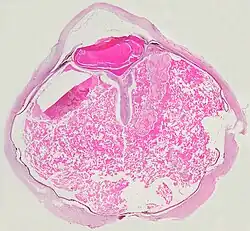

Microscopically, the wall of retinal vessels may be thickened in some cases, while in other cases the wall may be thinned with irregular dilatation of the lumen.[11] The subretinal exudate consists of cholesterol crystals, macrophages laden with cholesterol and pigment, erythrocytes, and hemosiderin.[12] A granulomatous reaction, induced by the exudate, may be seen with the retina.[13] Portions of the retina may develop gliosis as a response to injury.